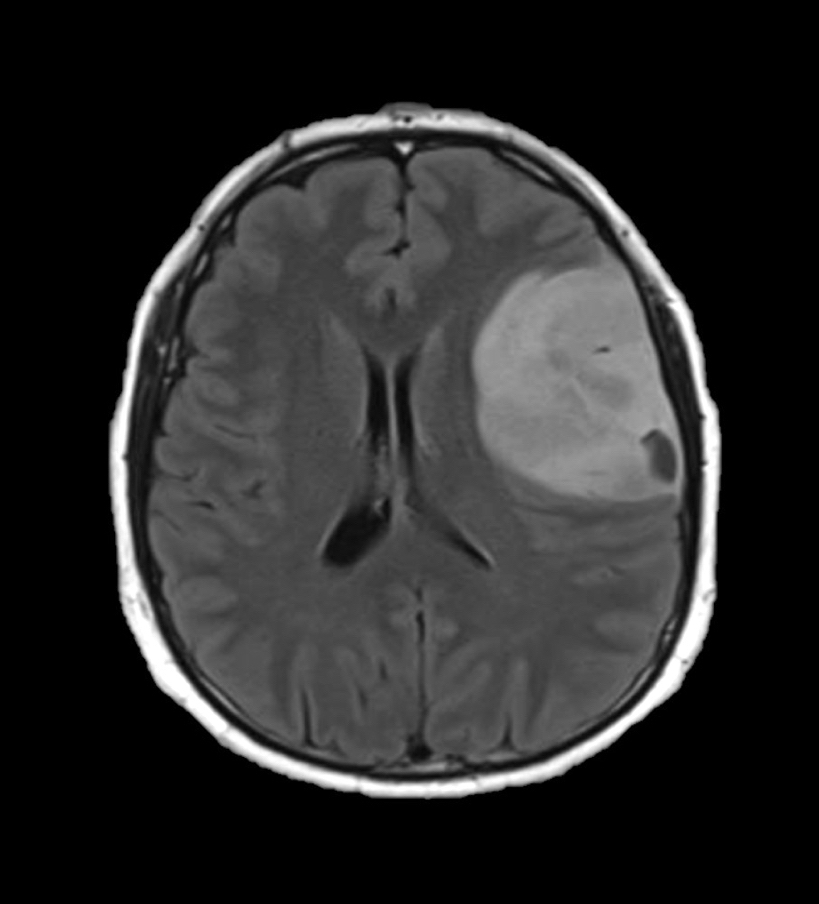

Radiology description

- CT:

- Expanding, intra-axial, poorly defined mass of low density

- Variable calcification may be seen

- Contrast enhancement and central hypodensity due to necrosis, occur with higher grades

- MRI:

- T1 hypodensity and T2 hyperintensity

- T2 hyperintensity with relative FLAIR sequence hypointensity (T2 FLAIR mismatch) is a relatively suggestive indication of IDH mutant astrocytoma (Clin Cancer Res 2017;23:6078)

- Distortion and enlargement of involved areas, including associated cortical ribbon

- Contrast enhancement is typically present in higher grade tumors (J Neurooncol 2019;141:327)

- Ring-like enhancement around central necrosis typical of grade 4

Radiology images